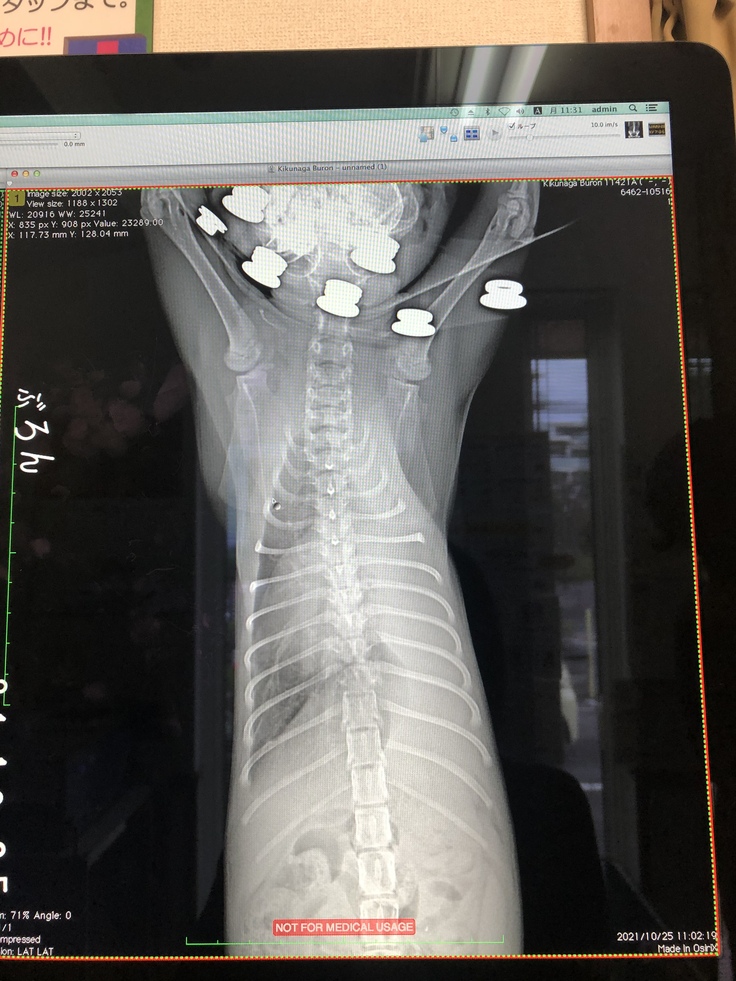

レントゲン検査の結果、左肺が真っ白に写っていました。胸腔内に胸水が溜まっていて、胸水が肺を圧迫していたたため、白くなっているのは酸素が入っていないことを示し、左肺がしぼんで機能していない状態でした(無気肺)。心音もほとんど聞こえない状態でした。この状態が続くと肺が元通りにはふくらまない、もしくは急にふくらんだ場合、毒素が全身に回り危険な状態になるという説明を受けました。

肺のレントゲン

レントゲン検査

無気肺の可能性があるため、肺のレントゲン検査を毎週とることになりました。

わずかですが、白い部分が減ってきています。